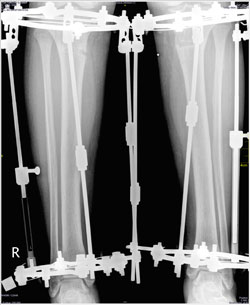

Рентген в 60 дней.

Рентген в 90 дней.

Приезжайте на снятие аппаратов!